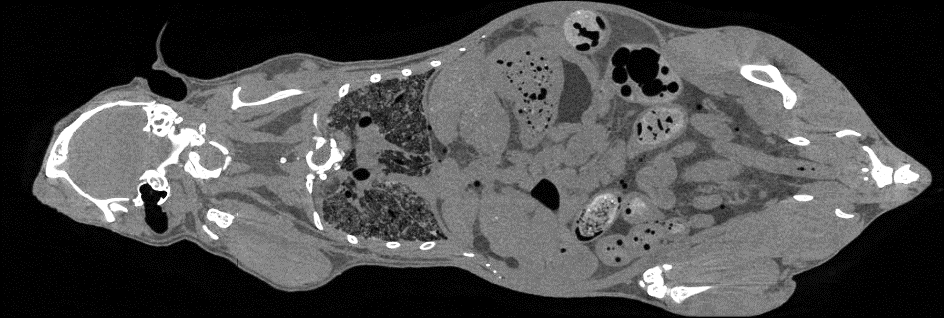

隨著臨床前研究向著活體成像、高分辨成像、多模成像等應用發展,傳統的顯微CT技術已無法滿足生命科學領域的研究需求。近年來,基于光子計數探測器的能譜CT已成為當前CT新技術的重要發展方向,高分辨X射線能譜CT成像技術正在快速發展。在中科院裝備研制等項目的支持下,項目團隊研發出國際首臺小動物活體能譜顯微CT設備,通過以微米級分辨及多能譜圖像再現動物體內的各器官組織的精細結構,實現動物實驗從離體到活體、從黑白到彩色的進步,為生物醫學研究提供更為先進的實驗手段和科學儀器。

小動物活體能譜顯微CT已經為國內科研院所、高校和醫院完成了一批高質量動物實驗,未來能夠為口腔疾病研究、骨研究、腫瘤研究、心血管疾病研究、生物材料研究和開發、新藥開發等多個領域提供先進的研究工具。

小動物活體能譜顯微CT設備

鼠全身成像

鼠釓劑造影成像